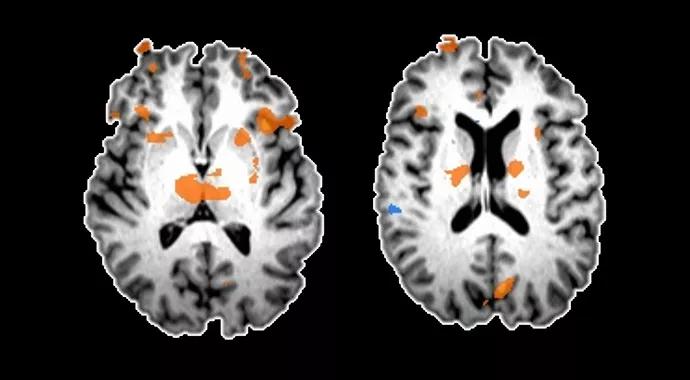

• We showed that it is possible to safely conduct fMRI studies in patients with fully implanted DBS systems. fMRI data were acquired during the blinded phase of the study and can therefore be correlated with the observed clinical improvements. The figure below shows an example of how fMRI can detect patterns of brain activity in a patient with an implanted DBS system. A striking difference is noted when comparing the fMRI data acquired when DBS was “on” vs. “off.”

Figure. Example of fMRI resting-state imaging showing the effects of DBS of the ventral striatal and ventral capsular areas on limbic networks.